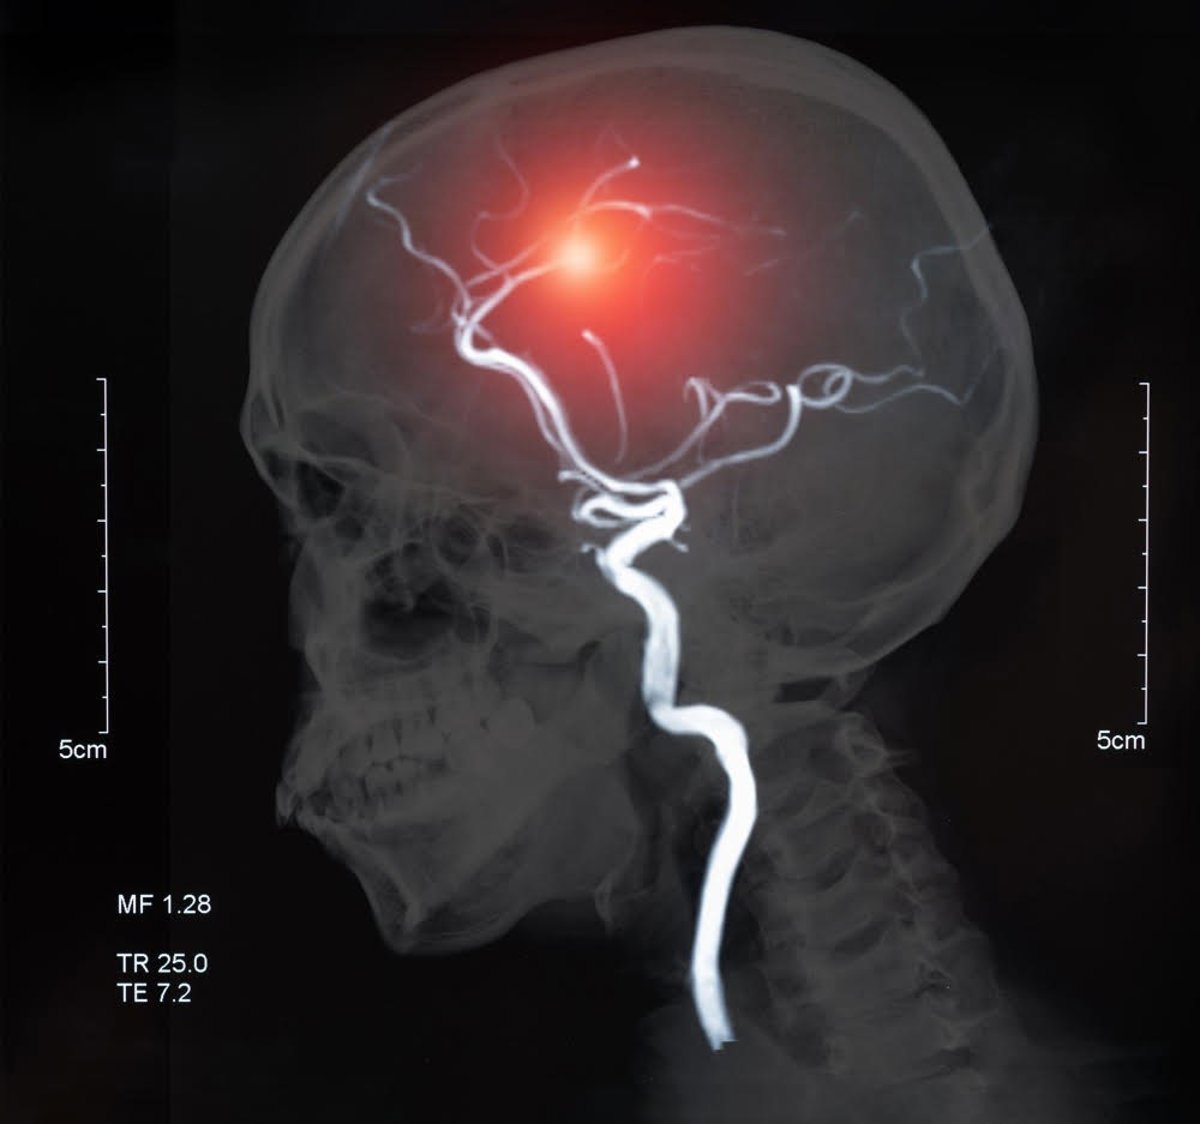

Archivo - Ictus

Archivo - Ictus - HOSPITAL LA LUZ - Archivo

Enfermedades como el ictus, Alzheimer y otras demencias, Parkinson o la ELA lideran en nuestro país los rankings de mortalidad y discapacidad, mientras que otras enfermedades neurológicas como la migraña, la epilepsia, o la esclerosis múltiple también contribuyen enormemente a la carga de discapacidad en España.

En los últimos 30 años, las cifras muertes por enfermedad neurológica han aumentado un 39% y los años de vida por discapacidad un 15%. Y solo en los últimos 10 años ya se ha duplicado el número de personas afectadas por enfermedades como la enfermedad de Parkinson y la demencia. Unas cifras que seguirán en aumento en los próximos años si no se toman medidas: se estima que en menos de 15 años el número de casos de ictus aumentarán un 35% y que en 25 años se triplicará el número de casos del Alzheimer y de Parkinson.

"La buena noticia es la gran mayoría de las enfermedades neurológicas pueden ser menos graves si cuidamos adecuadamente nuestro cerebro. Además, se ha demostrado que muchos casos pueden ser incluso prevenibles. Solo si tenemos en cuenta lo que la prevención podría suponer para tres de las enfermedades neurológicas más comunes en España, como son el ictus, la demencia o la epilepsia, estaríamos hablando de que cuidar adecuadamente nuestro cerebro podría evitar que más de 100.000 personas muriesen o viviesen con discapacidad cada año en España", destaca el Dr. José Miguel Láinez, presidente de la Sociedad Española de Neurología.